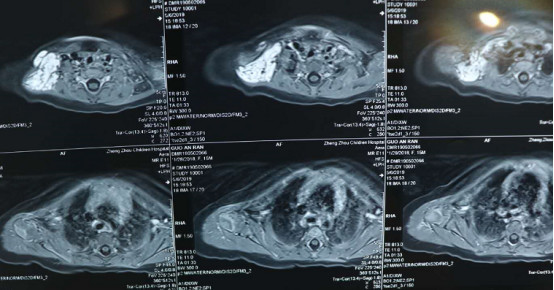

心情十分着急的晓妍妈妈立马带着晓妍来到郑大三附院,希望能够得到和其他医院不一样的治疗方案,让晓妍渐渐失去的笑容重新找回。乔军波主任在接诊晓妍后,仔细检查了晓妍的血管瘤位置,并为她进行了彩超检查,结果显示瘤体动静脉血流丰富并伴有异常搏动,存在明显动静脉瘘口。综合病情后,乔主任谨慎地对手术治疗的可行性进行了判断,给了晓妍妈妈坚实而有力的一句话:“尽快手术。”